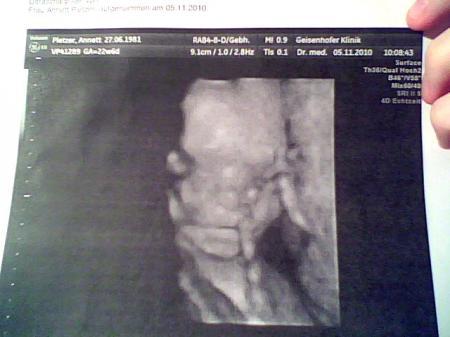

nach den Wochen des Wartens waren wir gestern nun endlich in München, und er hat keine Spalte, das hat mich echt fertig gemacht , es war eine fixe Idee dass er das auch hat und ja es war einfach schlimm. er wiegt nun 560gr und ist 29cm groß

Bild zu Gestern Pränataldiagnostik - Forum für März - Mamis

Schön, dass es Deinem Zwergl so gut geht und er schön gewachsen ist.... Sehr schöne Bildchen hast Du da. glg